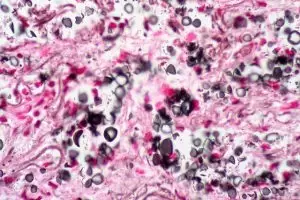

Kryptokokoza inna nazwa turoloza i drożdżycą europejską. To choroba grzybiczna powstała w konsekwencji działania grzyba drożdżopodobnego Cryptococcus neoformans z klasy grzybów niedoskonałych. Zachorowanie następuje w skutek osłabionego sytemu immunologicznego człowieka. Jeśli odporność jest na prawidłowym poziomie wówczas przebieg kryptokokozy jest bardzo łagodny, a objawy ustępują samoistnie.

Główną odpowiedzialność za kryptokokozę ponosi grzyb Cryptococcus neoformans. Warto więc wiedzieć gdzie możemy go spotkać tak aby w możliwie skuteczny sposób móc zapobiegać czy przeciwdziałać bliskim spotkaniom z tym przeciwnikiem. Otóż występuje on powszechnie w środowisku, szczególnie często w miastach zasiedlonych przez gołębie. Głównym źródłem zasiedlenia i rozprzestrzeniania się choroby jest ptactwo. W jaki sposób może dojść do zakażenia? Abyś mógł się zakazić, musi dojść do wprowadzenia do organizmu przez oddychanie lub rzadziej przez uszkodzoną skórę drobiny kurzu zanieczyszczonego odchodami gołębimi.

Wtórne zakażenia skóry mogą wystąpić nawet u 15% chorych z rozsianą kryptokokozą i często wskazują na złe rokowanie. Zmiany zwykle zaczynają się od pojawienia małych grudek, które następnie przechodzą w owrzodzenia, ale mogą też występować ropnie, guzki rumieniowe. Jeśli kryptokokoza zostanie rozpoznana u osoby zakażonej HIV, pozwala to na rozpoznanie pełnoobjawowego AIDS.